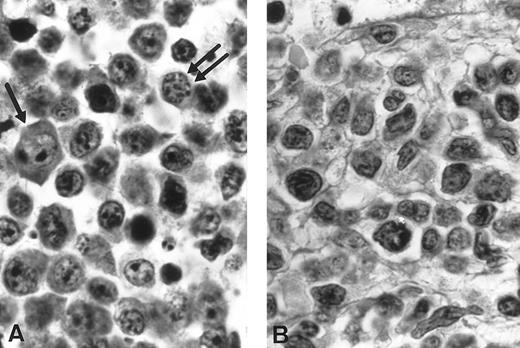

Histological findings (cases no. 1 and 2). (A) Case no. 1: High-grade T-cell lymphoma, large cell predominance; proliferation of large lymphoid cells with immunoblasts (arrow) and medium-sized cells with plasmacytic differentiation (double arrow). Notice the discrete nuclear pleomorphism (hematoxylin-eosin, original magnification × 1,320). (B) Case no. 2: High grade pleomorphic T-cell lymphoma, medium-sized and large cell predominance. Proliferation of lymphoid cells with irregularly indented nuclei of various size and small nucleoli looking like a pleomorphic T-cell lymphoma with predominance of medium cells (hematoxylin-eosin, original magnification × 1,320).